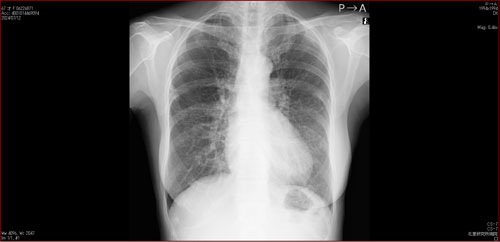

肺X線画像

- 2023.08.17 肺炎後の要観察(2)(国立系病院)